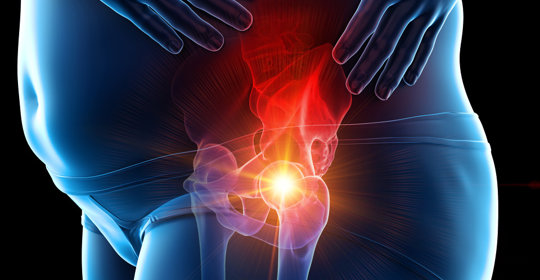

骨盆傷害:運動與治療策略

本文介紹了骨盆矯正運動,如腹肌訓練、臀橋練習、側身走動、拉伸放鬆以及核心穩定性鍛鍊。若在運動過程中出現疼痛或不適,應停止並尋求專業指導。骨盆歪斜可能有多種原因,如外傷後遺症、先天畸形或其他疾病狀態,處理方式各異。針對不同原因引起的問題,應尋求醫療幫助以獲得適當的治療方案。

骨盆歪斜:骨科、脊柱外科、康復醫學科、物理治療科

偏斜骨盆:外擴、錯位、術後遺症及痛感管理

骨盆傷害:矯正方法與坐墊使用

偏斜骨盆:症狀與影響